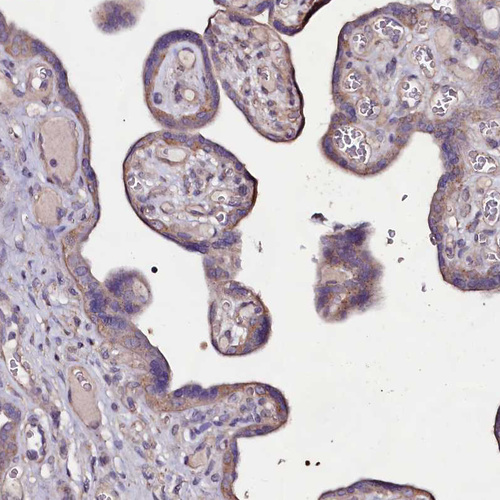

Immunohistochemical staining of human testis shows moderate cytoplasmic positivity in cells in seminiferous ducts.